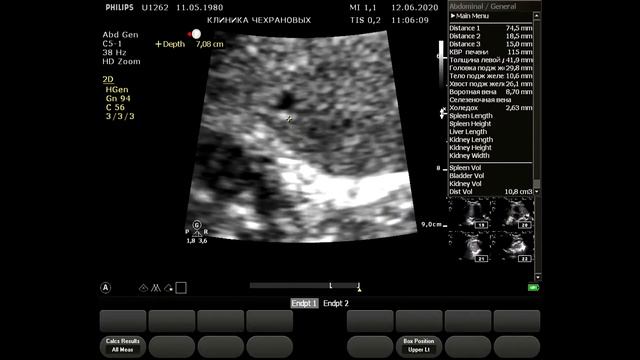

УЗИ БЦА - норма визуализация идеальная. Тот случай когда на обследование БЦА уходит 4 минуты без описания а описание минут 5-6. Для такой категории пациентов 20 минут на вполне достаточно. Но такой пациент скорее исключение из правил. УЗИ сердца - норма. На 12-й минуте - определение индексированного объема левого предсердия определение диастолической функции левого желудочка по тканевому допплеру.,